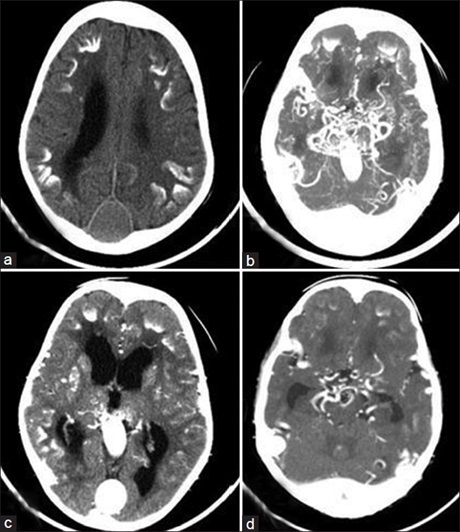

vein of Galen Aneurysmal Malformation in Children: Challenges of Imaging in An African setting

Dr. Godwin Inalegwu Ogbole, Amos Olufemi Adeleye, Richard Busayo Olatunji (Author)

45-49

Views | PDF/EPUB Downloads : 249 / 70 / 26

DOI: https://doi.org/10.82235/wajr.vol20no1.262